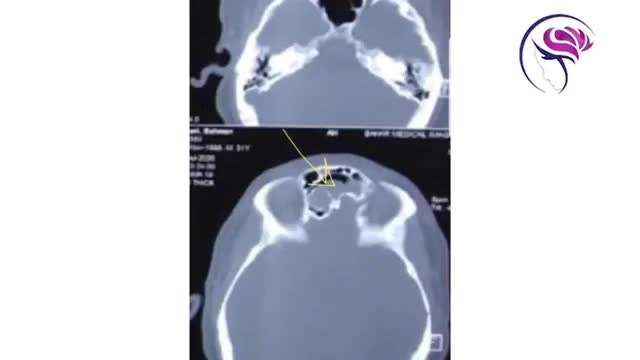

برای تشخیص موکوسل سینوس این فیلم را از دست ندهید!